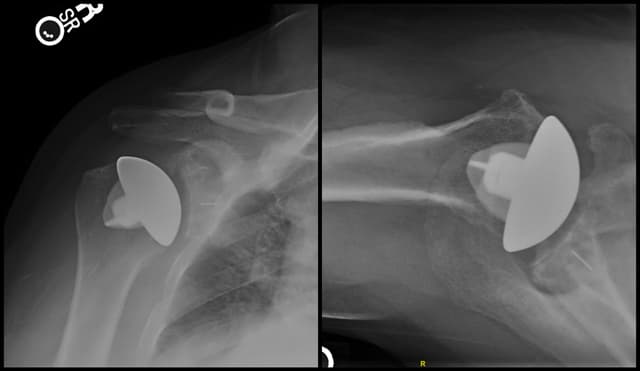

Post-op

Anatomic Total Shoulder Arthroplasty